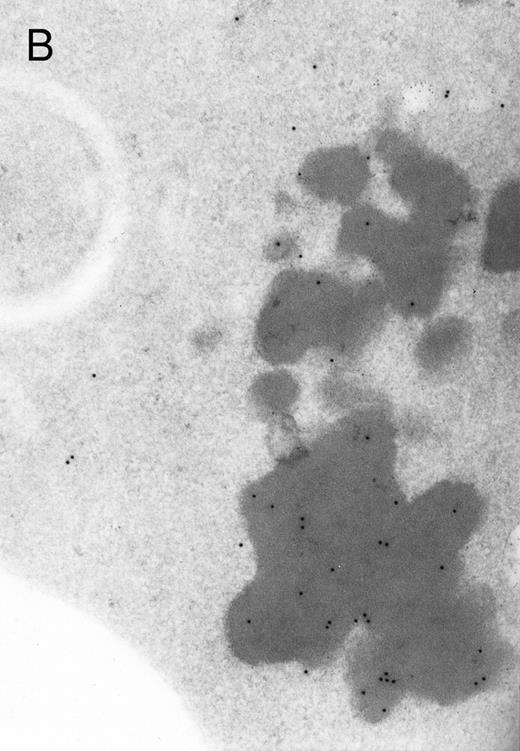

In both cases no. 1 and no. 2, electron microscope studies demonstrated electron-dense inclusions in 30% of early and late polychromatic erythroblast sections and many marrow reticulocytes. In ultrathin sections that reacted with monoclonal antibodies to either α- or β-globin chains followed by gold-labeled anti-mouse IgG, the density of gold particles over the majority of the inclusions was clearly greater than that over surrounding inclusion-free cytoplasm (Fig 3). By contrast, in sections from the two patients with β-thalassemia major, gold particles were concentrated over the inclusions following incubation with the antibody to α-globin chains, but not to β-globin chains (Fig 4A-C). The density of gold particles over inclusions in all control preparations was not greater than that over surrounding cytoplasm (Fig 4D).

Electron micrographs of erythroblastic inclusions from sections of marrow immunogold-labeled with mouse monoclonal antibody. Inclusions from case no. 1 show positive reactions with antibody against α-globin chains (A) and β-globin chains (B). Inclusions from case no. 2 show positive reactions with antibody against α-globin chains (C) and β-globin chains (D). Magnifications: A, × 32,000; B, × 38,000; C, × 32,000; D, × 37,000.

Prominent intra-erythroblastic inclusions were also present in both of these individuals (patients no. 1 and 2) with dominantly inherited β thalassemia. The percentage of polychromatic erythroblast sections containing inclusions in the two cases was 30%, which is considerably above the range (0.2% to 2.8%) previously reported in β-thalassemia trait.13 We have investigated the composition of the inclusions in cases no. 1 and 2 by immunoelectron microscopy using mouse monoclonal antibodies against human α- and β-globin chains and the immunogold technique. The intra-erythroblastic inclusions in the two cases reacted with both monoclonal antibodies to α- and β-globin chains, clearly indicating that these inclusions contained both types of chains. In contrast, the intra-erythroblastic inclusions found in homozygous β thalassemia reacted with the monoclonal antibody against α globin but not β-globin chains, confirming that they consisted only of precipitated α-globin chains. These data support the hypothesis that the cellular pathology underlying the dominantly inherited β thalassemias is related to the synthesis of highly unstable β-globin chains, which are not able to form functional tetramers. These abnormal β-chain variants precipitate intracellularly together with the concomitant excess α-globin chains to form large inclusions, which leads to more severe ineffective erythropoiesis than in heterozygous β thalassemia, in which much smaller amounts of precipitated globin chains are found.17